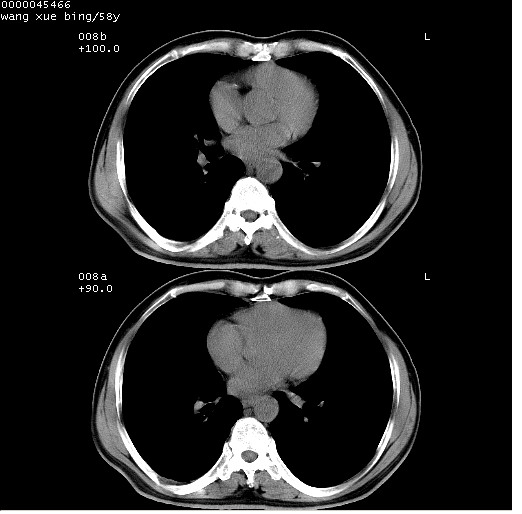

胸部ct轴位平扫(层厚10mm,螺距1.5,重建间隔10mm),图像如下:

考虑右下肺中心型肺癌并远端阻塞性炎症及胸膜及纵隔淋巴转移

支持癌性空洞并远端阻塞性炎症